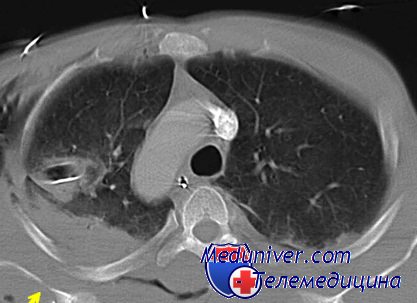

Рентгеновские снимки тератомы средостения: Диагностика и лечение

Раздел: Фотоэссе